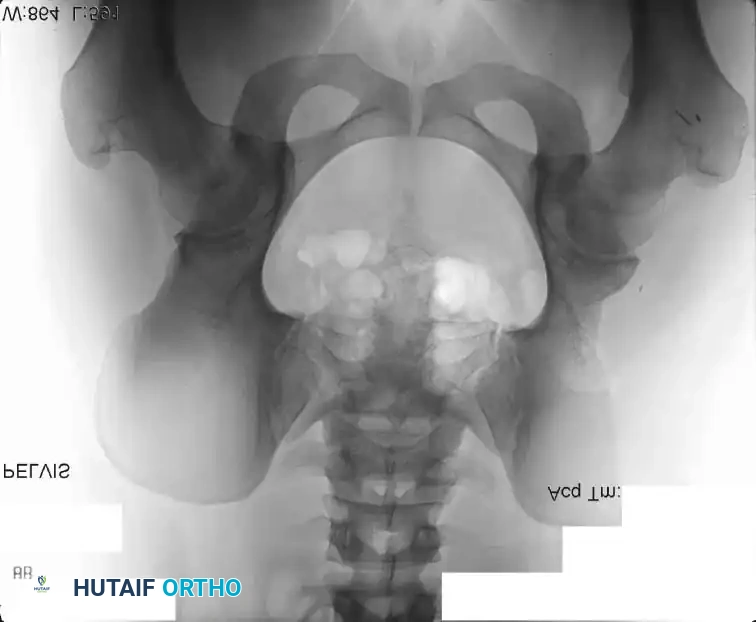

Intraoperative Imaging and Margin Assessment

Continuous intraoperative assessment using fluoroscopy and frozen section pathology is mandatory. The following images demonstrate various stages of complex upper extremity resections, allograft preparations, and prosthetic implantations across the humerus and elbow joint.